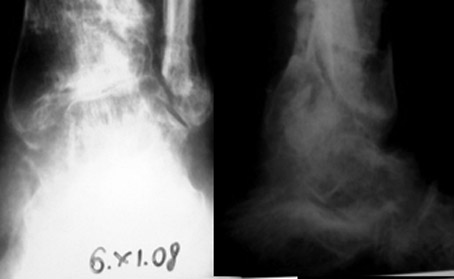

Больной К 45 лет,

ДЗ: ложный сустав левой голени.

Травма 1 год назад, ТСТ. открытый фрагментарный перелом левой голени, перелом мыщелков левой голени, н.з малоберцовой кости. +плечо, Алкогольный делирий.

В настоящий момент левая нижняя конечность не опорная, имеется патологическая подвижность в с.з голени. Раны зажили более 6 мес назад.